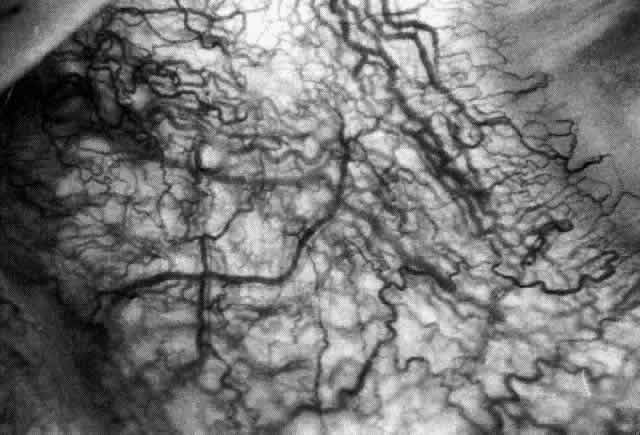

The sclera that is edematous is pushed forward, and the deep episcleral network is more congested than the superficial networks (Figs. 27 and 28). It is usually easy to ascertain by simple observation that the patient has scleritis and not episcleritis. However, it is not as easy to ascertain whether the patient has early necrotizing scleritis. It is in these patients that fluorescein angiography has considerable value, because the first changes are detectable in the ocular vasculature. Prompt and adequate treatment can prevent these changes from becoming irreversible.

Fig. 27. In scleritis, maximum congestion occurs in deep episcleral plexus, which is bowed forward by underlying scleral edema. Episcleral tissue is slightly infiltrated and superficial plexus is slightly congested (see Fig. 14). (Watson PG, Hayreh S, Awdry P: Episcleritis and scleritis. Br J Ophthalmol 52:278–279, 1968)

Fig. 28. Nodular scleritis. Both the anterior conjunctival slit and the deep scleral slit are displaced forward by the scleral edema. There is little separation between these two beams, indicating that all the edema is in the sclera and not in the overlying episclera. (Watson PG, Hayreh S, Awdry P: Episcleritis and scleritis. Br J Ophthalmol 52:278–279, 1968)

Diffuse Anterior Scleritis

Diffuse anterior scleritis is the most common and least severe type of scleritis. The inflammation is widespread, and it may involve either a small segment or the whole of the anterior segment, sometimes with such severe overlying inflammation as to justify the name “brawny” scleritis (Fig. 29). On slit lamp examination, the vascular pattern of both deep and superficial layers may be distorted, so that the normal radial pattern of the vessels is lost; large anastomotic channels develop, leading to beading and tortuosity of the remaining vessels (Figs. 30 and 31; Color Plate 1C).